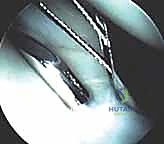

Wrist Arthroscopy: The Gold Standard

- Diagnostic Superiority: Wrist arthroscopy has become the criterion standard for both diagnosing and treating TFCC lesions. It offers unparalleled accuracy in determining the exact location, size, and stability of tears, and whether a flap is unstable or impinging.

- Concomitant Lesions: Arthroscopy also allows for the identification and treatment of coexisting pathologies, such as tears within the lunotriquetral interosseous ligament, ECU subsheath tears, or chondral lesions of the carpus or distal ulna.